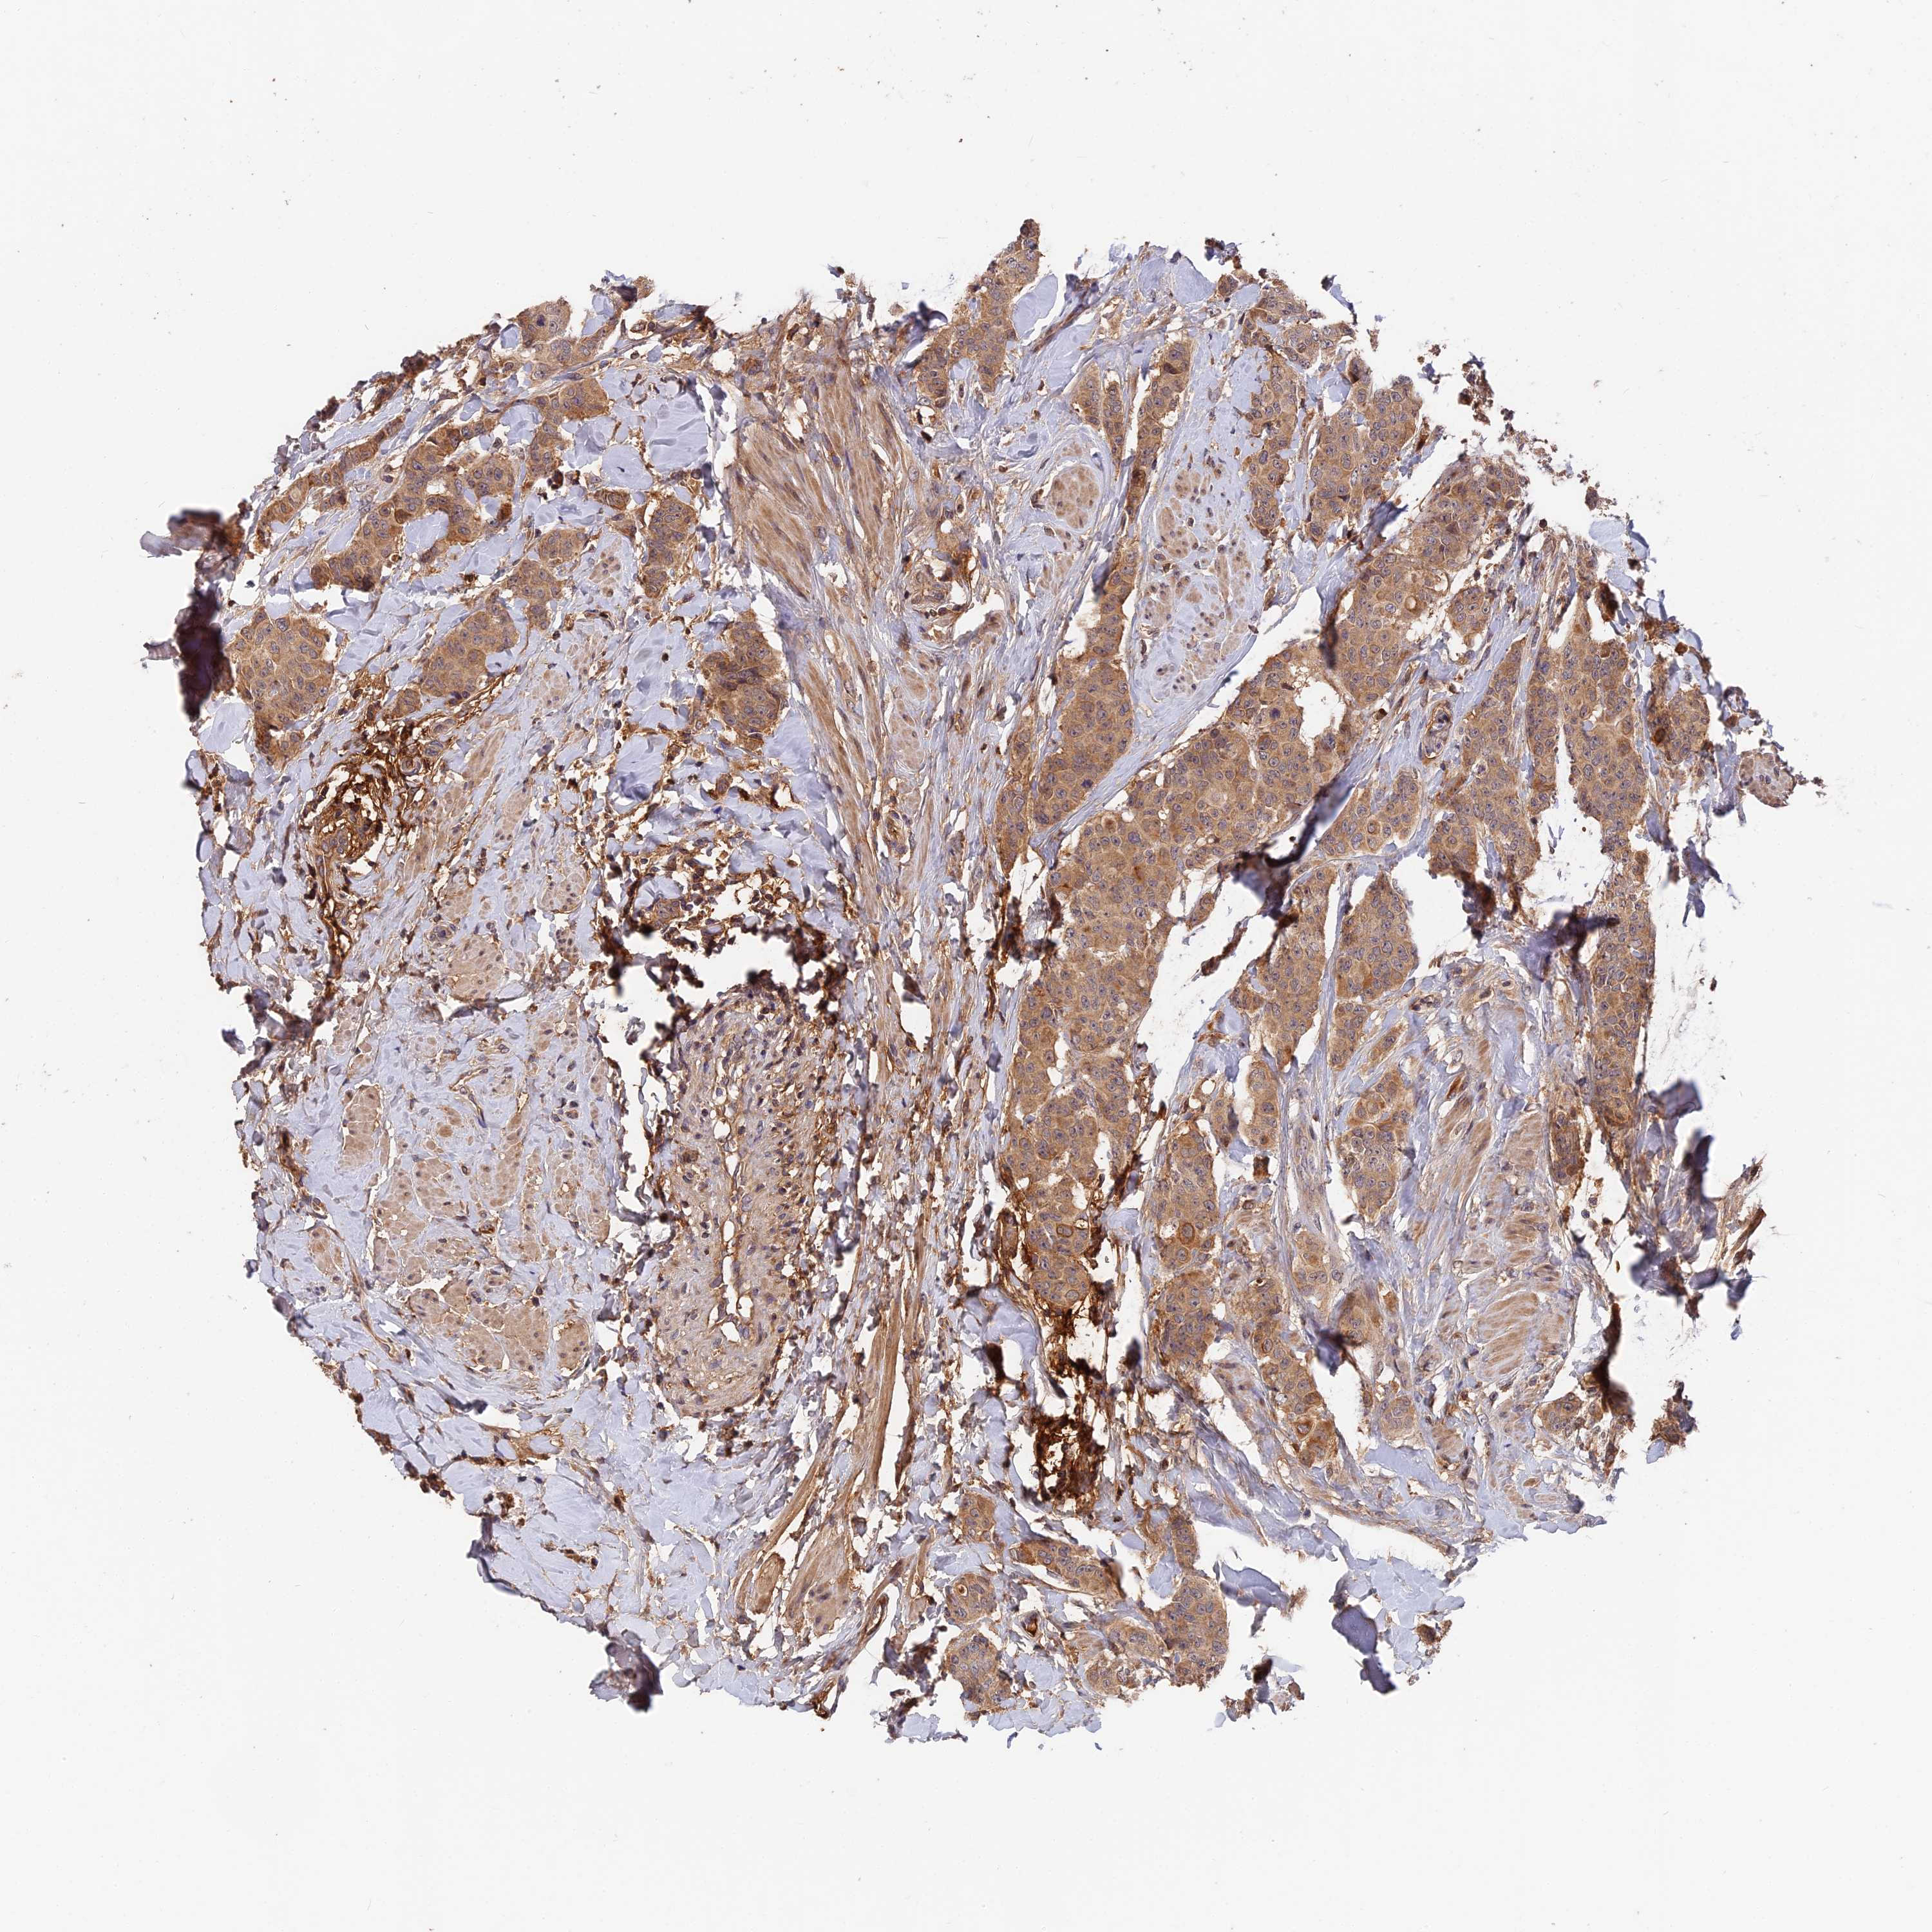

CANCER BREAST CANCER Show tissue menu

BRCA TCGA BRCA VALIDATION PROTEIN EXPRESSION